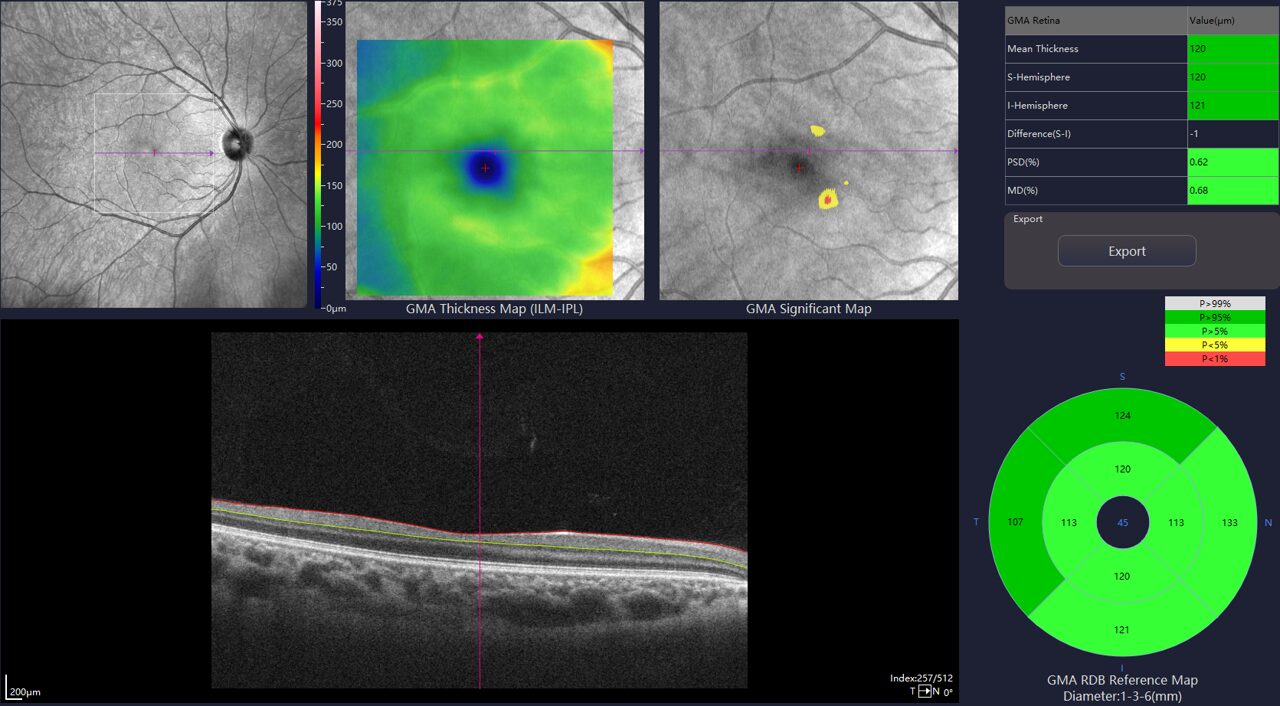

Ganglion Cell Complex analyse

- Ideale predictor om vroegtijdig glaucoom op te sporen en op te volgen

- De GMA diktekaart wordt vergeleken met de normatieve database om snel via kleurcodes een evaluatie te kunnen maken

- De PSD en de MD zijn bijkomende factoren die de graag van vroegtijdig verlies en de uitgebreidheid evalueren.